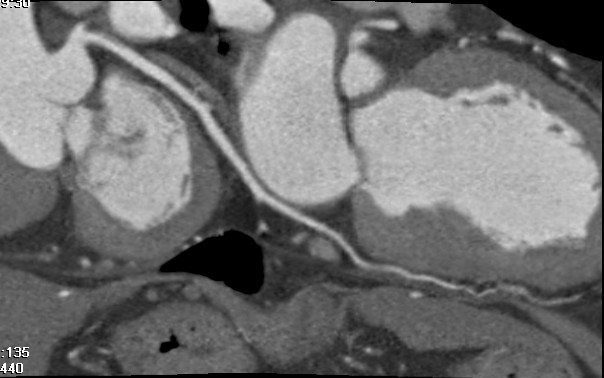

标题: CT24400:患者54岁,心前区不适进行心脏冠脉造影检查。 [打印本页]

标题: CT24400:患者54岁,心前区不适进行心脏冠脉造影检查。

患者54岁,心前区不适进行心脏冠脉造影检查。高手看看有问题没有?

图像很漂亮,好像未见异常